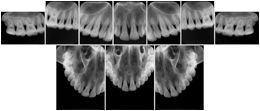

Intra-oral radiography typically involves acquisition of multiple images of various parts of the dentition. Many digital radiographic systems offer customized templates that are used for displaying the images in a study on the screen. These templates may also be referred to as mounts or view sets. The Structured Display Object represents a standard method of encoding and exchanging the layout and intended display of Structured Displays. A structured display object created in this manner could be stored with a study and exchanged with images to allow for complete reproduction of the original exam.

1. A patient visits a General Dentist where a Full Mouth Series Exam with 18 images is acquired. The dentist observes severe bone loss and refers the patient to a Periodontist. The 18 images from the Full Mouth Series along with a Structured Display are copied to a DICOM Interchange CD and sent with the patient to see the specialist. The Periodontist uses the CD to open the exam in his Dental Radiographic Software and consults via phone with the General Dentist. Both are able to observe the same exam showing the images on each user's display using the exact same layout.

Intra-oral Full Mouth Series Structured Display

Figure OO-1. Intra-oral Full Mouth Series Structured Display